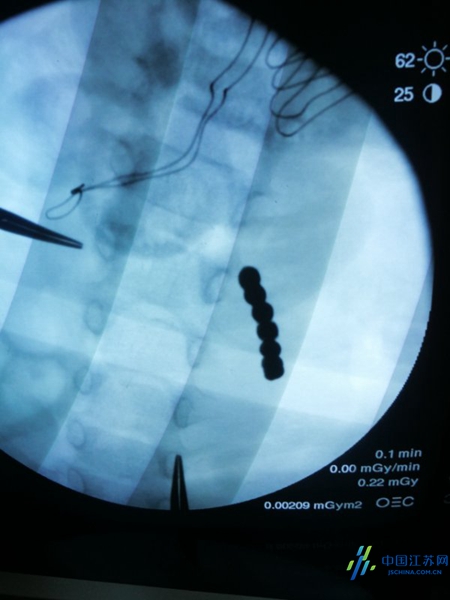

小宇被转往儿外科进一步治疗,南医大二附院儿童外科团队郭俊斌主任、汪锋、周巍和许晶晶医生在详细检查后发现,小宇已经有腹膜刺激征的表现,可能已经引起消化道穿孔,在与家长充分沟通后,决定立即手术将异物取出,否则小宇可能会有生命危险。术中,郭俊斌主任探查发现在小宇的空肠部位盘踞着一串金属珠子,切开肠腔,取出了24颗磁力珠,这些磁力珠互相紧紧的黏在一起,随后又在胃里取出10颗珠子。当取出34颗珠子的时候,郭主任发现在小宇胃幽门和十二指肠的连接处水肿严重,而且弹珠数与术前阅片数量不符,必定有残留的磁力珠。于是立即进行手术台边的X线拍摄导航,显示在某个位置仍盘踞着一部分磁力珠。小宇的十二指肠已经出现两处穿孔,有消化液不断流出,最后在穿孔处又取出了7颗珠子,共计整整41颗。手术成功后,小宇的病症终于得到好转。